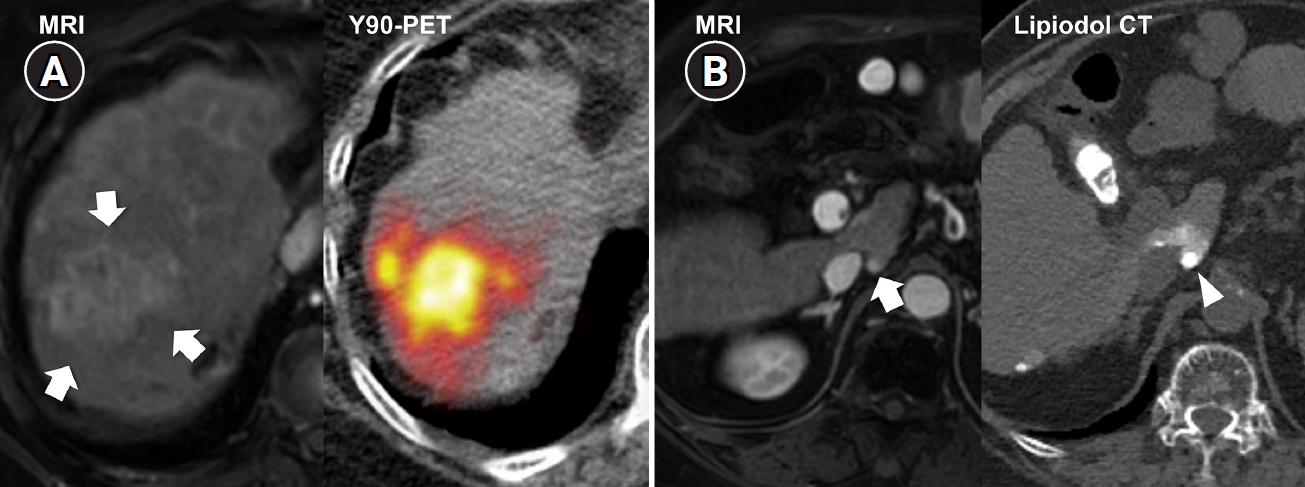

Fig. 1.

Radiation subsegmentectomy in an 86-year-old man with a single nodular hepatocellular carcinoma. (A) Liver magnetic resonance imaging shows a 2.2-cm hypervascular tumor (arrow) with exophytic growth in segment 6. (B) Hepatic arteriography shows a hypervascular tumor (arrows), and the microcatheter was advanced into a subsegmental branch of A6 (right side image). A total activity of 0.35 GBq of glass microspheres was infused. (C) Post-treatment Y-90 positron emission tomography shows intense uptake at the tumor (arrow), confirming a perfused liver dose of 508.7 Gy and a tumor dose of 1,794.7 Gy. Voxel-based dosimetry showed a D95 of 625 Gy and a V200 of 100% (D95: the minimum dose delivered to 95% of the target volume, V200: the percentage of target volume receiving ≥200 Gy). (D) Twenty-month follow-up computed tomography shows complete response with dystrophic calcification (arrow).

Recent advances in dosimetry optimization have markedly improved the therapeutic outcomes of TARE. Radiation segmentectomy and radiation lobectomy have expanded the role of TARE from a palliative treatment to a potentially curative modality. In early or localized HCC, radiation segmentectomy can achieve complete necrosis by delivering ablative radiation doses confined to one or two hepatic segments (Fig. 1). In the LEGACY study, which included patients with solitary HCCs (median diameter, 2.7 cm; range, 1.0 to 8.1 cm), radiation segmentectomy achieved a 2-year complete response (CR) rate of 84% [12]. In the RASER trial, a single-center prospective study conducted in patients with solitary HCCs ≤ 3 cm, the initial objective response rate was 100 % [18]. This outcome was superior to that reported in a Korean retrospective study (2-year CR rates in 1–10 cm HCCs: 66.2% with conventional TACE and 30.5% with drug-eluting bead TACE [DEB-TACE]) and a Japanese randomized controlled trial (3-month CR rates in 1–5 cm HCCs: 75.2% with conventional TACE and 27.6% with DEB-TACE) [19,20]. Several studies have further demonstrated that radiation segmentectomy can achieve local tumor control rates comparable to those of surgical resection or local ablation, when appropriate dosimetry is achieved [21]. Even for multifocal or bulky tumors, Korean investigators have expanded this principle beyond segmentectomy into a broader concept of radiation “major hepatectomy,” applying ablative doses to larger anatomical territories when disease remains confined and hepatic reserve is adequate (Fig. 2). A Korean study reported a median time to progression of 17.1 months in patients with tumors averaging 11.4 cm in size treated at mean absorbed doses of 418.8 Gy [22]. Radiation lobectomy can also be used when resection is technically feasible but unsafe because the future liver remnant (FLR) is insufficient [23]. By intentionally delivering sufficient radiation dose to non-tumorous parenchyma in the target lobe, contralateral hypertrophy can be induced while simultaneously suppressing tumor progression in the treated lobe [24]. Taken together, these results indicate that territory-based TARE with high radiation dose can serve as a reasonable alternative in patients who are technically resectable but medically inoperable, or in those initially considered for resection who later become unsuitable because of comorbidities or limited hepatic reserve [25].